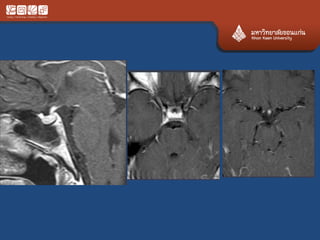

Pituitary Macroadenoma

• Usually soft

• Elevate diaphargma selle

• Often contrasted at diaphargmatic hiatus as

tumor growth into the suprasellar cistern

• Snowman shape

• *commonest large tumor of the skull base